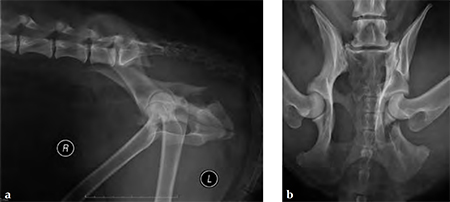

A 4-year-old Gordon setter suffered a road traffic accident and sustained multiple pelvic fractures.

(Case provided by Michael Kowaleski, North Grafton, USA)